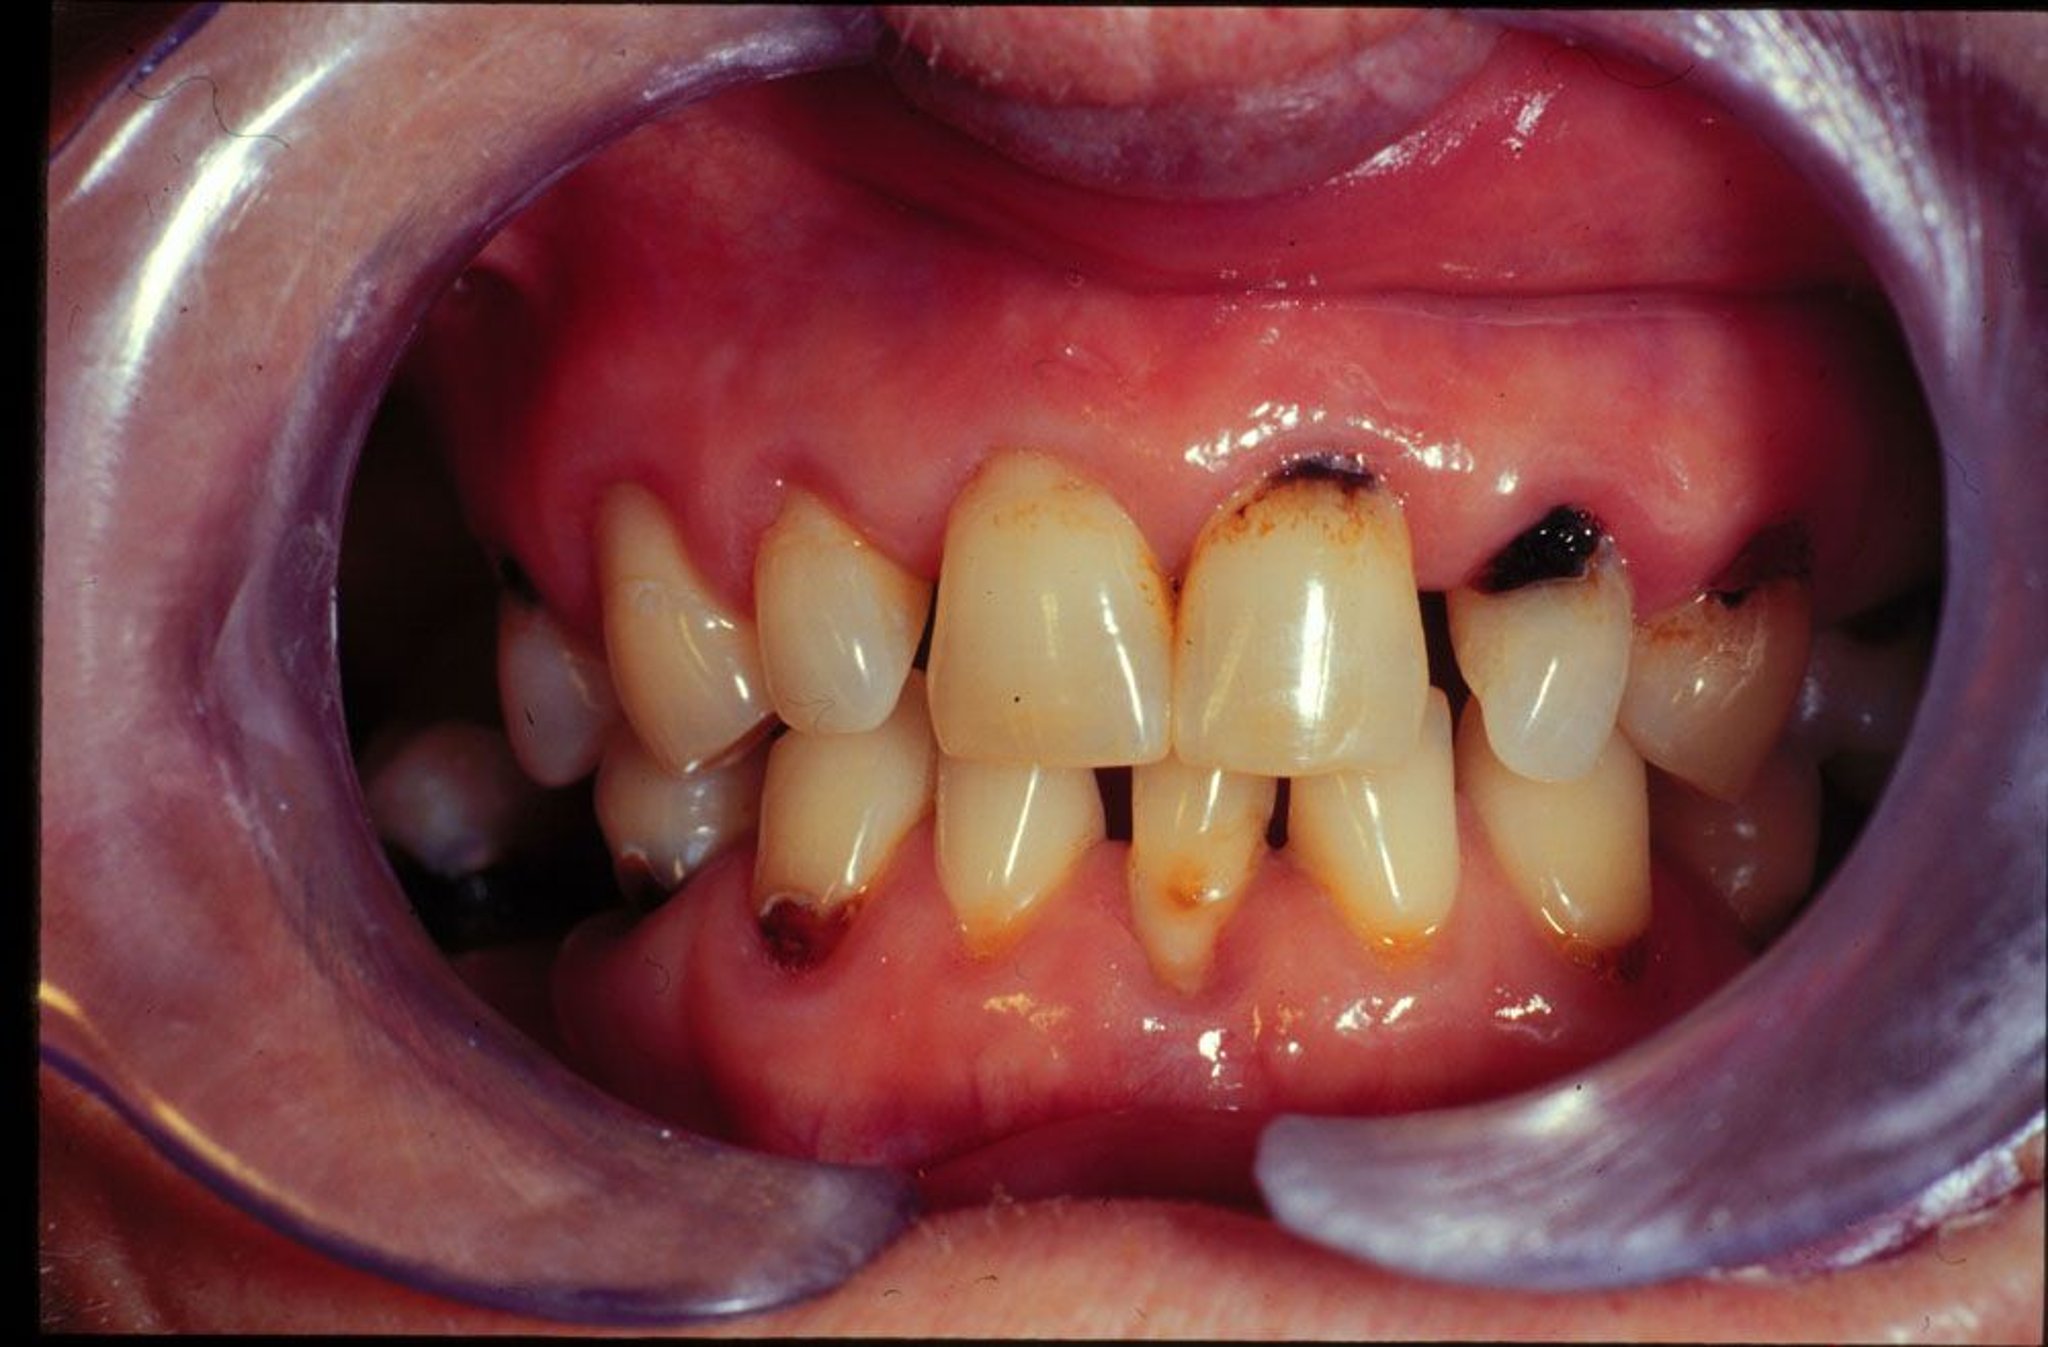

Caries dentaires nouvelles et récurrentes chez un patient qui a la bouche sèche.

Image provided by Jonathan A. Ship, DMD.